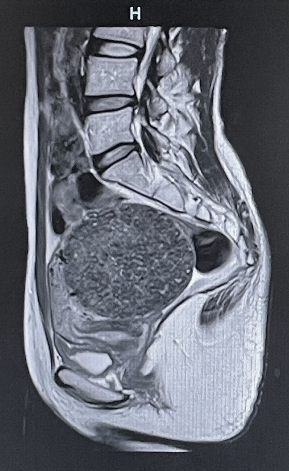

MRI検査とは

MRIとは磁気共鳴断層画像診断装置(Magnetic Resonance Imaging )の略です。

原理:強い磁石の中に入り、電波を与えることにより体の中の水素原子が共鳴します。

電波を止めると水素原子から微弱な電波が出ます。

MRI検査この微弱な電波を使って画像を作る検査です。